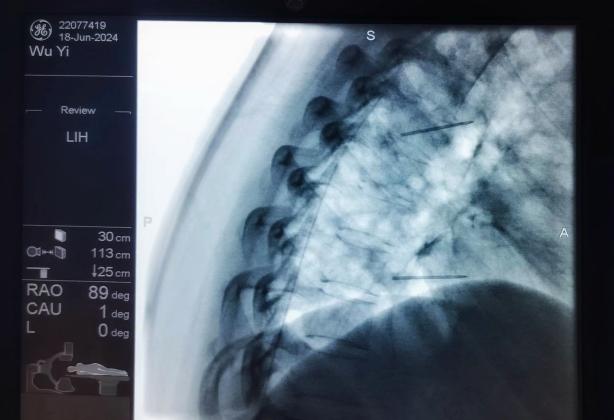

射頻消融治療,連續射頻或脈沖射頻對椎間盤或神經進行干預治療,目的是減小神經根周圍的壓力及對神經的調控治療,從而達到緩解癥狀的效果;

膠原酶椎間盤化學溶解術,是在影像引導下(C型臂X線機或CT),將膠原酶準確地注射到突出的椎間盤內及其周圍,使突出的椎間盤溶解并吸收,解除其對神經根的壓迫,進而緩解癥狀。